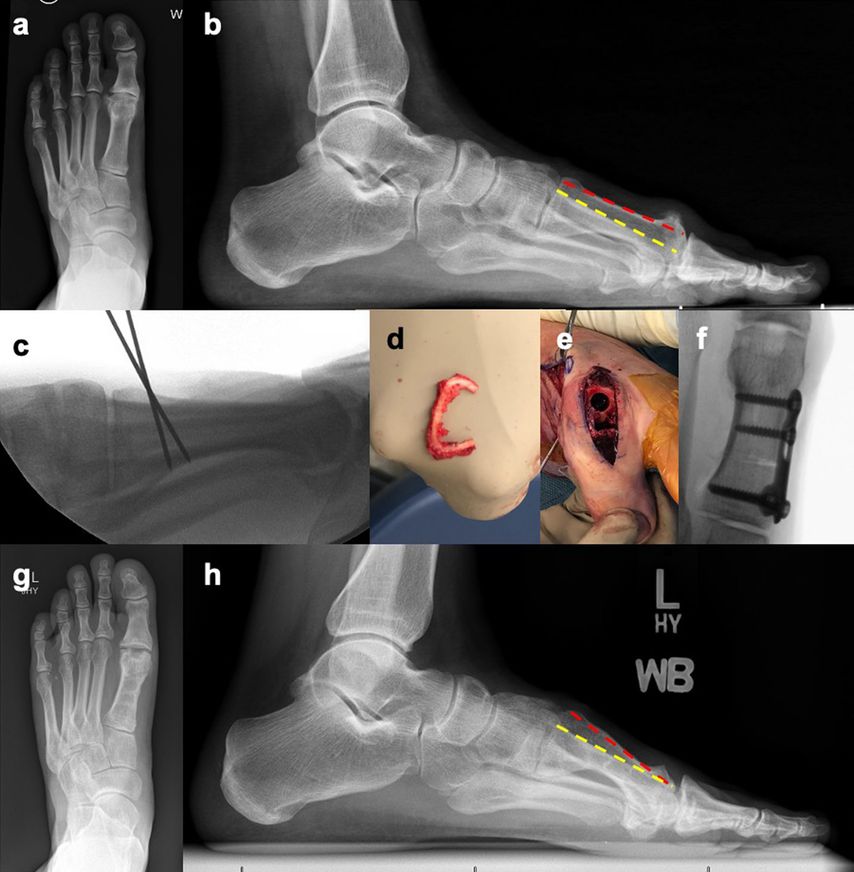

Wir bevorzugen eine plantare „Closing wedge“-Osteotomie, die mit einer Cheilektomie oder auch einer zusätzlichen Moberg-Osteotomie kombiniert werden kann (Abb. 2).

Abb. 2: 46-jähriger Patient mit einem symptomatischen Hallux rigidus mit Elevation des 1. Strahls und einer Gastrocnemius-Kontraktur: a) a/p-Röntgen (Rö) mit Gelenksspaltverschmälerung und Osteophyten, b) Laterales Röntgen zeigt eine Elevation des Metatarsale (MT) 1 (rot) in Relation zum MT 2 (gelb). Der operative Plan inkludierte eine endoskopische Gastrocnemius-Rezession, eine plantare flektierende und verkürzende plantare „Closing wedge“-Osteotomie des proximalen Metatarsale 1 sowie eine Cartiva®-Implantation, c) Intraoperatives laterales Rö zeigt die geplante plantare „Closing wedge“-Osteotomie, d) Resektion plantarer Kortex des MT1, e) Präparation und Implantation eines 10mm-Cartiva®-Implantates, f) intraoperatives a/p-Rö nach Osteosynthese mit winkelstabiler Platte und Cartiva®-Implantation, g), h) 2 Jahre postoperativ a/p- und laterales Rö. Eine Metallentfernung fand in der Zwischenzeit statt. Der Patient zeigt eine verbesserte plantarflektierte Position des MT1, ein kongruentes Gelenk mit guter Beweglichkeit und Schmerzfreiheit